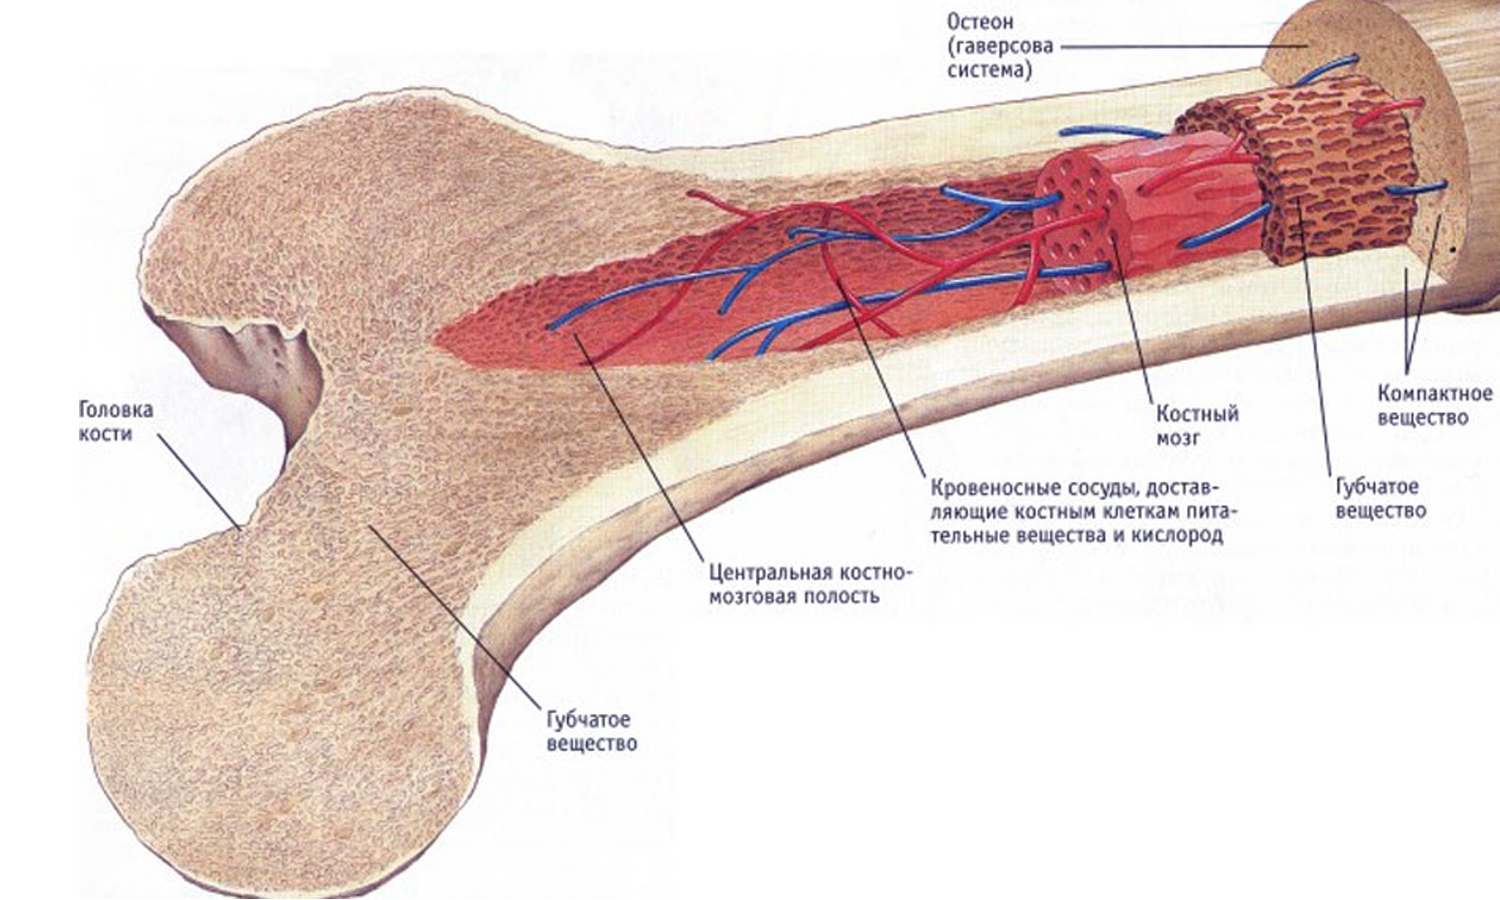

Изучение костного мозга: анатомия и функции

Раздел: Фотогалерея мыслей